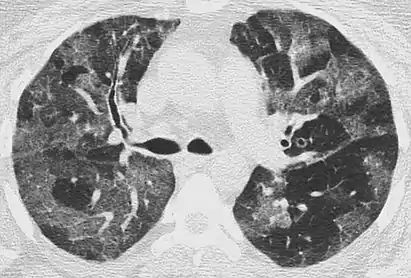

Mosaic

A mosaic pattern of GGO refers to multiple irregular areas of both increased attenuation and decreased attenuation on CT. It is often the result of occlusion of small pulmonary arteries or obstruction of small airways leading to air trapping.[6] Sarcoidosis is an additional cause of a mosaic GGOs due to the formation of granulomas in interstitial areas. This may coexist with granulomatosis with polyangiitis, leading to diffuse areas of increased attenuation with ground-glass appearance.[6]

CT image showing mosaic attenuation pattern in patient with hypersensitivity pneumonitis. Note the alternating, patchy areas of increased and decreased attenuation, particularly in the left lung (screen right).